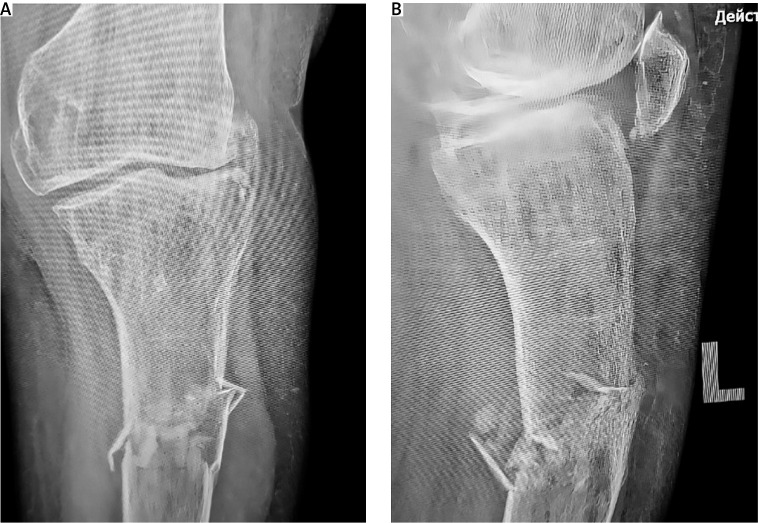

骨折延迟愈合是骨科实践中常见的并发症,尤其是骨质疏松症患者。再生医学的进步,包括间充质干细胞(MSCs)在基质血管部分,引入了新的治疗方法来解决这一挑战。本病例描述了一位患有绝经后骨质疏松症和左下肢先天性异常的患者,其胫骨近端骨折伴碎片移位。骨质疏松治疗开始,骨折使用外固定和压迫处理。尽管在8个月的时间里骨密度有所改善,但x线评估显示没有骨折愈合的证据。因此,在骨折部位进行局部给药联合针刺,然后进行一系列自体浓缩血浆(ACP)注射。3个月内,观察到骨痂形成的影像学征象,最终在开始再生治疗6个月后骨折完全愈合。尽管我们临床病例数量有限,无法对骨折愈合的主要促进因素得出明确的结论,但现有文献表明,骨折部位高浓度内源性资源的动员促进了组织再生。身体活动和辅助药物治疗进一步促进了这一过程。结合MSCs和acp衍生生长因子的再生疗法是治疗系统性骨质疏松患者骨折并发症的一种有希望的辅助方法。这种策略有可能促进骨愈合,同时可能延迟甚至避免需要更多的侵入性手术干预。

Delayed fracture union is a common complication in orthopedic practice, particularly in patients with osteoporosis. Advances in regenerative medicine, including mesenchymal stem cells (MSCs) within the stromal-vascular fraction, have introduced novel therapeutic approaches to address this challenge. This case describes a patient with postmenopausal osteoporosis and a congenital anomaly of the left lower limb who sustained a proximal tibial fracture with fragment displacement. Osteoporosis therapy was initiated, and the fracture was managed using external fixation and compression. Despite an improvement in bone mineral density over an eight-month period, radiographic assessment revealed no evidence of fracture union. Consequently, local administration of MSCs combined with needling at the fracture site was performed, followed by a series of autologous concentrated plasma (ACP) injections. Within three months, radiographic signs of bone callus formation were observed, ultimately leading to complete fracture union six months after the initiation of regenerative therapy. Although the limited number of cases in our clinic prevents definitive conclusions regarding the primary contributing factor in fracture healing, existing literature suggests that the mobilization of endogenous resources at the fracture site in high concentrations promotes tissue regeneration. This process is further facilitated by physical activity and adjunctive pharmacological treatment. Regenerative therapy integrating MSCs and ACP-derived growth factors represents a promising adjunctive approach for managing fracture complications in patients with systemic osteoporosis. This strategy has the potential to enhance bone healing while potentially delaying or even avoiding the need for more invasive surgical interventions.